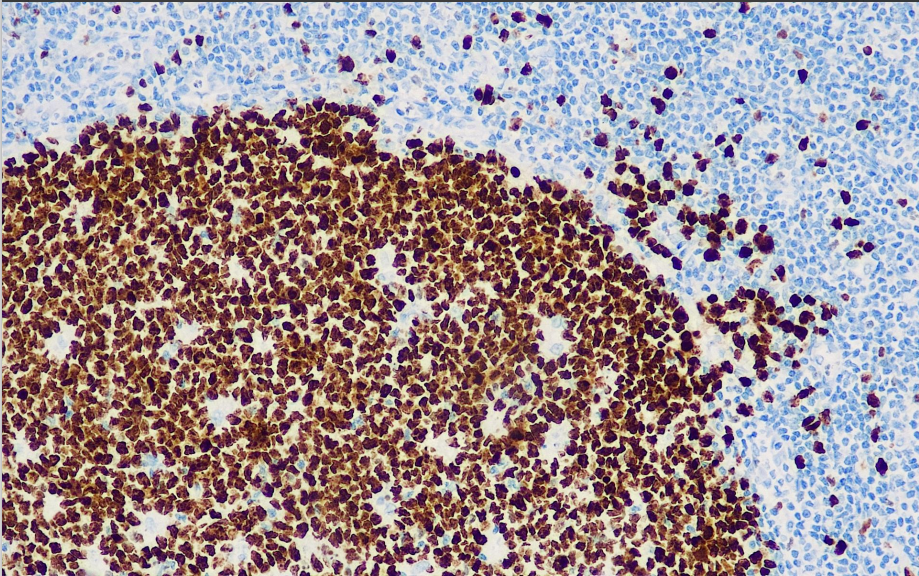

Positive control: tonsils/breast cancer

Ki-67 recognizes cells in cell cycles other than the G0 phase, and is used to determine the proliferative activity of cells, and is a marker for determining the growth status of benign and malignant tissues. Studies have shown that it is closely related to histologic typing of breast cancer and lymph node metastasis. Therefore it is an important reference index for the prognosis of certain malignant tumors.

The Ki-67 antibody reagent can specifically bind to the Ki-67 molecular antigen. The immunohistochemical kit containing the Ki-67 light chain antibody reagent is suitable for the assessment of tumor proliferation activity.